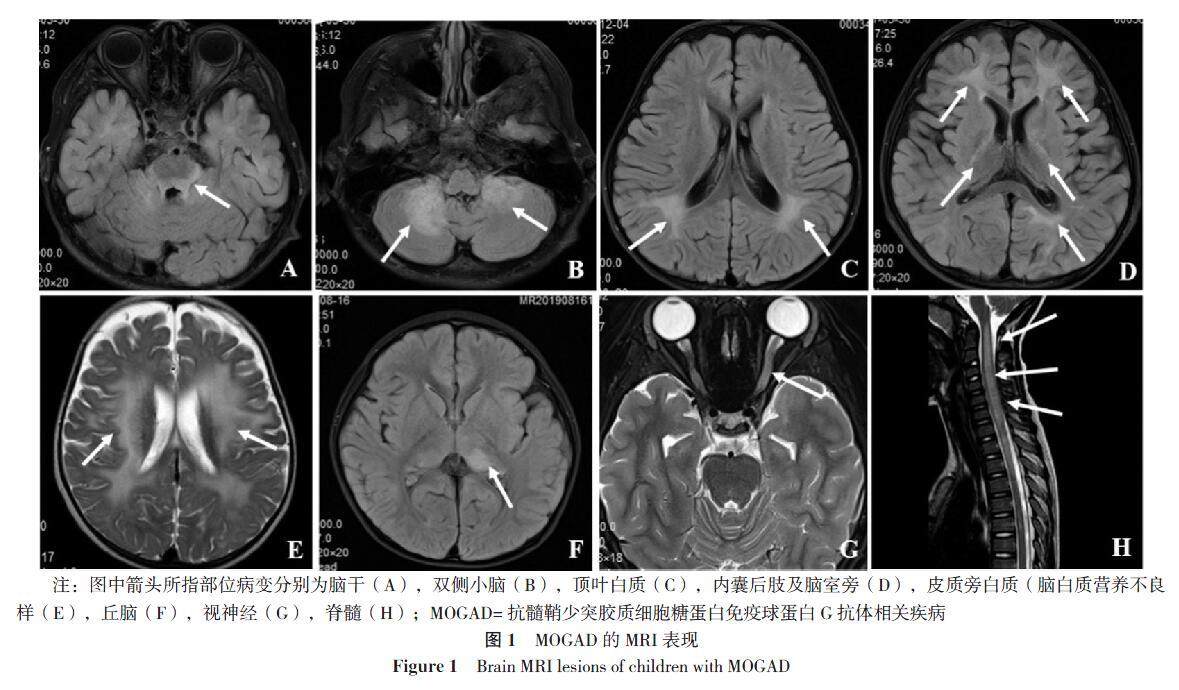

【摘要】 背景 抗髓鞘少突胶质细胞糖蛋白(MOG)免疫球蛋白G抗体相关疾病(MOGAD)在儿童中的比例明显高于成人。目前在儿童中MOGAD相关表型的特征及与复发风险的联系仍未明确。目的 观察儿童血清MOG免疫球蛋白G抗体(MOG-IgG)阳性的中枢神经系统(CNS)脱髓鞘疾病的表型特征及复发因素。方法 对河北省儿童医院2017年12月至2021年12月确诊的54例MOGAD的儿童进行随访研究,回顾性分析每次发作时的临床表型、实验室检查、影像学特点、血/脑脊液的MOG-IgG滴度变化、疗效及复发高危因素。(剩余16323字)